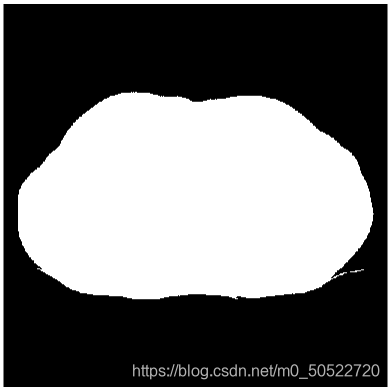

迭代分割是逼近思想,将通过程序不断迭代出所需要的阈值,再对图像二值化处理。将背景与人体进行分离,背景的灰度值赋值为0,人体的灰度值赋值为255。即可得到二值图。

(4)二值图像连通区域标记(人景分割)和图像孔洞填充

使用图像孔洞填充消除肺质中的孔洞。连通分量标记(或者称连通分量分析,连通区域标记)是图论应用中的一种算法,给二值图像中的每个连通区域标上一个特定的标号。该算法可用来对图像的目标进行定位和计数。已知每个孔洞的一个点后,我们的目的就是用前景像素填充所有孔洞。